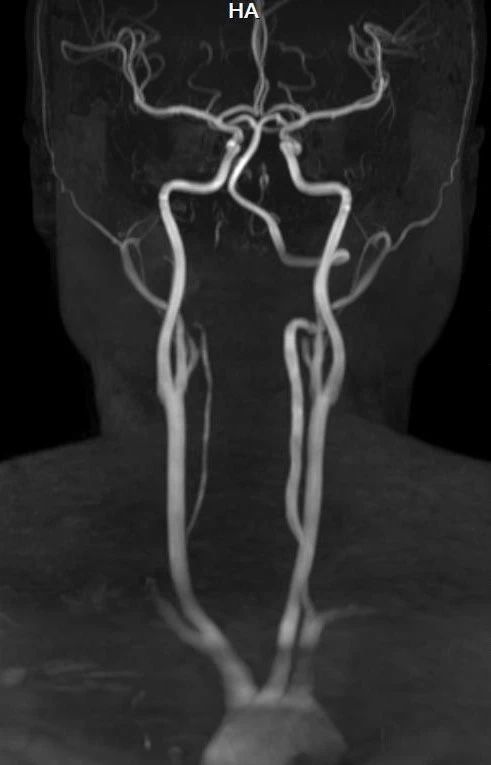

随着脑血管疾病发病率的攀升,早期筛查成为预防脑卒中、动脉瘤破裂等严重后果的关键。高场强头颈部磁共振血管成像(MRA)凭借其独特优势,逐渐成为高危人群脑血管筛查的重要工具。以下从适用人群、检查优势及不足三方面,为您解析这项技术的应用价值。

一次检查可同时观察头颈部动脉主干及分支,结合平扫还能评估周围脑组织是否受损(如缺血灶),适合筛查脑卒中或复杂血管病变。